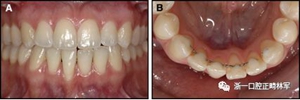

圖13.粘合到尖牙和切牙上的柔性螺旋弓絲保持器,伴有牙齦退縮和附著喪失,中切牙之間嚴(yán)重的扭矩差異以及兩顆尖牙的橫向移動和扭矩。牙周問題和牙齒移動的嚴(yán)重程度均為牙周正畸聯(lián)合治療的指征:A,正面視圖; B,咬合面視圖。

圖14.三維立體圖像:A,面部和B,切牙根部的舌側(cè),剛?cè)〕龉潭ㄉ鄠?cè)保持器后。